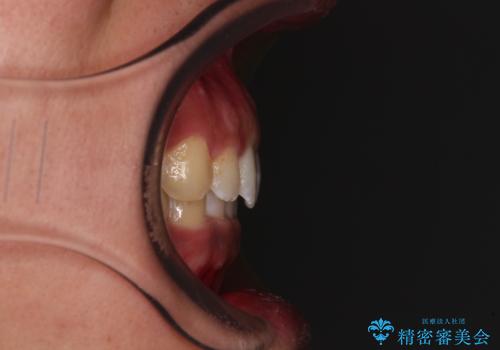

- 前歯のデコボコや隙間と深い咬み合わせ(ディープバイト)を気にして来院された患者様です。

インビザラインによる上下歯列の側方拡大と後方移動、IPR(歯と歯の間を削る)にるスペースの獲得により、デコボコとディープバイトを改善することとしました。

気になっていたデコボコや隙間は改善し、きれいな歯列に整えることができました。

咬合力が非常に強い方であったため、これ以上のディープバイトの改善は困難となりました。